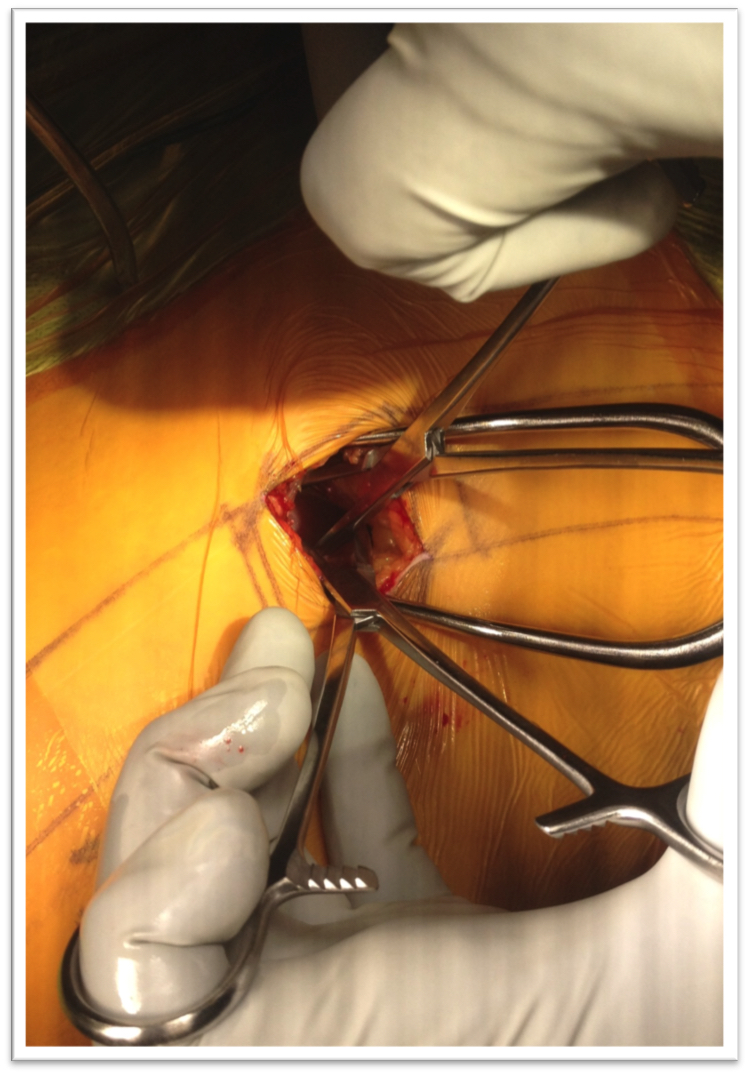

6. Berjano P, Gautschi OP, Schils F, Tessitore E. Extreme lateral interbody fusion (XLIF®): how I do it. Acta Neurochir (Wien) 2015;157(3):547-51. doi: 10.1007/s00701-014-2248-9

19. Guerin P, Obeid I, Bourghli A, Masquefa T, Luc S, Gille O, et al. The lumbosacral plexus: anatomic considerations for minimally inva- sive retroperitoneal transpsoas approach. Surg Radiol Anat 2012;34(2):151-7. doi: 10.1007/s00276-011-0881-z

36. Moller DJ, Slimack NP, Acosta FL Jr, Koski TR, Fessler RG, Liu JC. Minimally invasive lateral lumbar interbody fusion and transpsoas approach-related morbidity. Neurosurg Focus 2011;31(4):E4. doi: 10.3171/2011.7.FOCUS11137